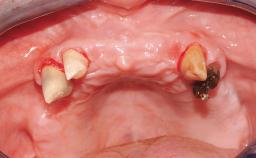

A fully edentulous 65-year-old woman was referred to our clinic for esthetic and functional dental rehabilitation. The patient presented with inadequate complete maxillary and mandibular prostheses, insufficient vertical dimension, and extensive tooth wear. The clinical examination and anamnesis showed no local or systemic contraindications, no signs or symptoms of bruxism, and an absence of smoking habits. The treatment proposed was implant placement in the mandibular interforaminal area and immediate loading with a fixed definitive prosthesis. A removable mucosa-supported complete prosthesis was indicated for the upper jaw, since its bone structure offered satisfactory retention and the financial condition of the patient disfavored a full-mouth implant-supported rehabilitation.

Case Type Edentulous Mandible

Jaw Mandible

Area Full-Arch